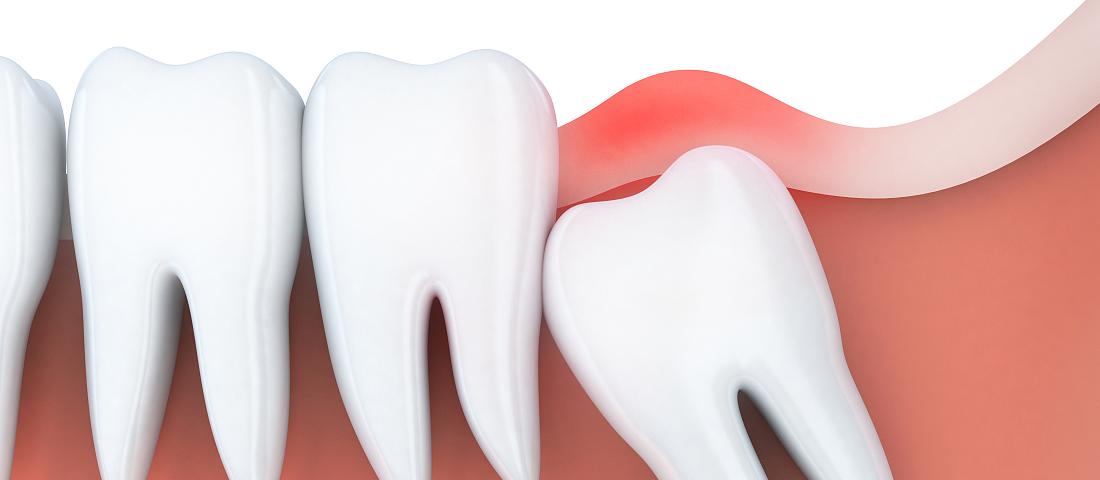

我们通常所讲的会造成严重后果的智齿,都是指下颌智齿。那么可能引起严重后果的下颌智齿又有哪些情况呢?如下图:

近中阻生

大家千万注意,长成以上类型的智齿都可能发炎,如果不对它们进行及时的处理,任由它发展下去的话,便会导致很严重的后果。所以对于上述所讲情况的智齿,都应该引起一定的重视,最好尽早将智齿拔除。

智齿发炎会导致周围的牙龈红肿、疼痛,龈袋溢脓,并发间隙感染,张口受限,面颊瘘,更严重的还会导致菌血症、败血症而是危及生命。所以对于发炎的智齿我们千万不能放任不管,最好在控制炎症后尽快进行拔除。